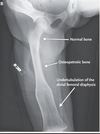

**BQ!** What disease is from osteoclastic failure and is a result of sclerosis of the bone with thickening of the cortex and filling of marrow cavity, “Erylenmeyer Flask”? What is another name for this disease they could use on boards?

Osteopetrosis aka Albers-Schonberg Disease ## Footnote Associated anemia, extramedullary hematopoiesis, hypersplenism, and infection. Bones are brittle and fracture. Bone is dense and trabeculae have cores of cartilage. While there may be abundant osteoclasts, they are not functional and fail to resorb calcified cartilage.